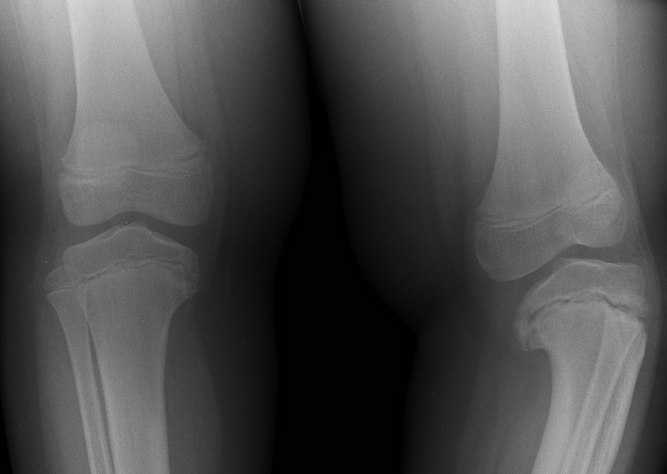

Genu varum

Bowlegs:

demographics: is a common finding in infants and toddlers younger than 2 years of age.

treatment: Improvement occurs spontaneously with time, and most children have straight legs by the time they are 2 years old.

Blount:

A few children with bowlegs, however, continue to progress and worsen, and in some cases the bowing is unilateral. This is termed Blount disease and is characterized by an abnormality in the medial aspect of the proximal tibial epiphysis.

Labs: Radiographically there is a prominent step abnormality with beaking at the proximal tibial epiphysis.

Treatment: Aggressive treatment is essential, as the disease can be rapidly progressive and lead to permanent growth disturbances. Bracing can be effective up to the age of 3; later correction may require surgery. Blount disease can occur in several forms: infantile (ages 1-3 years), juvenile (ages 4-10 years), and adolescent (age 11 years and older). Clinically, the findings are the same; in the adolescent group, radiograph findings are less prominent.